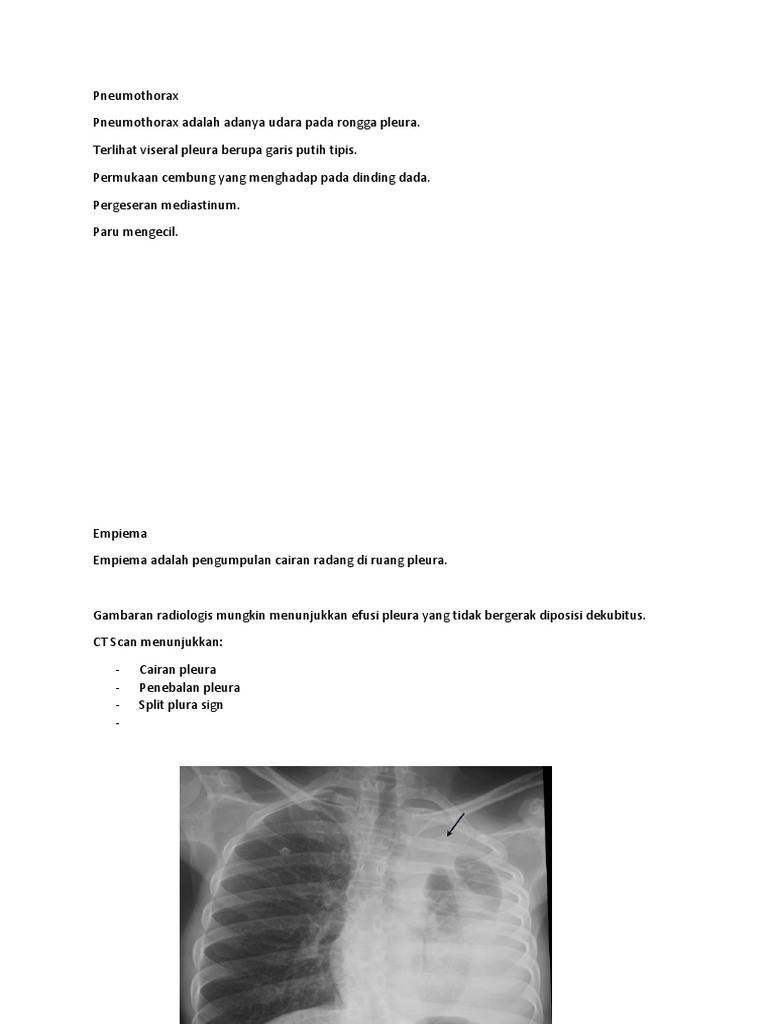

Empiema Docx